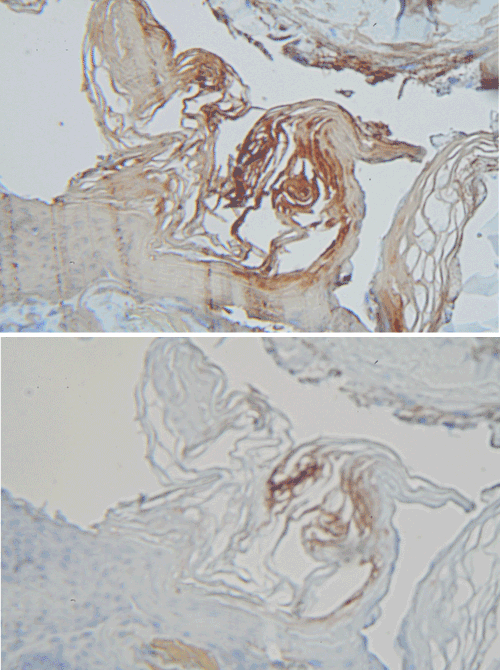

Keratin immunostaining

The results of keratin immunostaining experiments are shown in Figure 6. The MD filaments from Case 1 stained strongly with the “pankeratin” antibody AE1/AE3 directed against cytokeratin 1/3. In contrast, the filaments stained weakly with the more restrictive antibody AE5/AE6 directed against cytokeratin 5/6. Staining with AE1/ AE3 was seen over the length of the fiber, while staining with AE5/ AE6 was only detected in the outermost scale. Melanin pigmentation was not seen in the fibers. No staining was detected with an irrelevant monoclonal antibody, and similar positive keratin staining with AE1/ AE3 was detected in MD fibers from Case 2 (data not shown).

Figure 6: Keratin immunostaining of fiber from Case 1. Immunostaining was performed as described in Methods section. Top: Staining with anti-CK AE1/ AE3. Bottom: Staining with anti-CK AE5/AE6 (200x magnification).

The present study demonstrates Morgellons filaments that clearly originate from a layer of pavement epithelial cells visibly held together by desmosomes (Figure 2). The predominant cells found in pavement epithelial tissue are keratinocytes. We also noted MD fibers that clearly originate from the inner root sheaths of hair follicles (Figures 2-4), and keratinocytes are the predominant cell type in this tissue. Keratinocytes produce the biofiber keratin. A cross section of BDD filaments likewise demonstrates filament origin from cells beneath the stratum corneum (Figure 5), consistent with descriptions in the literature of growth from keratinocytes [14,19]. Thus MD filaments and BDD filaments appear to be similar in formation at the cellular level, both originating from keratinocytes in the stratum spinosum or stratum basale. MD differs from BDD, however, in that MD filaments appear to originate from follicular keratinocytes as well as epidermal keratinocytes. Both MD filaments and BDD filaments fluoresce in UV light (Figures 2-5). We have also shown for the first time that MD filaments contain keratin (Figure 6), and keratin staining was positive using a “pankeratin” monoclonal antibody but negative with a more restricted keratin ligand. This observation indicates that the fibers originate from specific tissues that require further characterization.